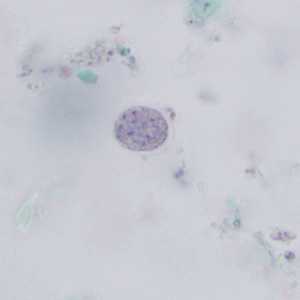

E. coli cysts stained with trichrome.

Figure A: Immature cyst of E. coli, stained with trichrome. Notice the presence of only two nuclei, and a large glycogen vacuole.

Figure B: Mature cyst of E. coli, stained with trichrome. Five nuclei are visible in this focal plane.

Figure C: Mature cyst of E. coli, stained with trichrome. In this specimen, at least five nuclei are visible in the shown focal plane.

Figure D: Mature cyst of E. coli, stained with trichrome. In this specimen, at least five nuclei are visible in the shown focal plane.

Figure E: Mature cyst of E. coli, stained with trichrome. This figure and Figure F represent the same cyst shown in two different focal planes. Eight nuclei can be seen between the two focal planes. Also, above the cyst in this figure, a trophozoite of Endolimax nana can be seen.

Figure F: Mature cyst of E. coli, stained with trichrome. This figure and Figure E represent the same cyst shown in two different focal planes. Eight nuclei can be seen between the two focal planes.